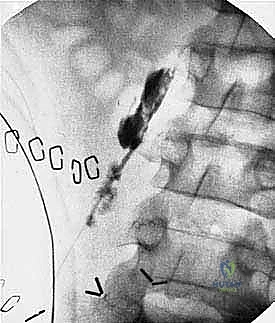

- التصوير بالرنين المغناطيسي (MRI): هو المعيار الذهبي لتقييم أورام العظام والأنسجة الرخوة. يوضح للدكتور هطيف الامتداد الدقيق للورم داخل نخاع العظم ومدى غزو العضلات والأوعية الدموية المجاورة.

- التصوير المقطعي المحوسب (CT Scan): لتقييم التدمير العظمي بدقة، وللبحث عن أي انتشار للورم (نقائل) في الرئتين أو أجزاء أخرى من الجسم.

- التصوير المقطعي بالإصدار البوزيتروني (PET Scan): لتحديد النشاط الأيضي للورم واكتشاف أي بؤر سرطانية دقيقة في الجسم.

- الخزعة (Biopsy): الخطوة الأهم لتأكيد التشخيص. يقوم الدكتور هطيف بإجراء خزعة بالإبرة الأساسية (Core Needle Biopsy) بدقة متناهية، مع مراعاة أن يكون مسار إبرة الخزعة ضمن المنطقة التي سيتم استئصالها لاحقاً أثناء البتر، لمنع انتشار الخلايا السرطانية.